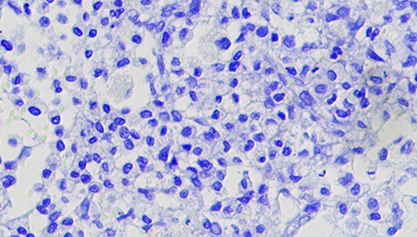

瑞氏-吉姆萨染色 原理 步骤

瑞氏-吉姆萨染色(Wright-Giemsa Staining)原理:瑞氏染料由酸性染料伊红和碱性染料亚甲蓝组成。血红蛋白、嗜酸性颗粒为碱性蛋白质,与酸性染料伊红结合呈红色;细胞核蛋白和淋巴细胞胞浆为酸性蛋白质,与碱性染料美蓝或天青结合,呈紫蓝色;中性颗粒呈等电状态与伊红和美蓝均可结合,呈淡紫色。吉姆萨染料由伊红,天青组成...